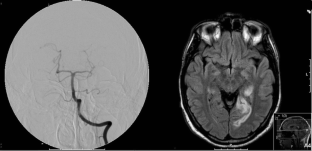

Fig. 1